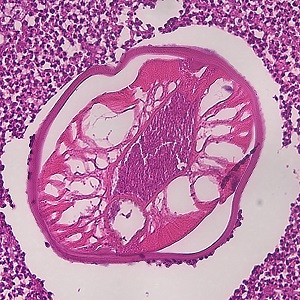

Case #479 – November, 2018

A 29-year-old female with a nodule on her left back was examined at a university hospital in Belgium. The nodule was excised and sent to pathology. Figures A – C show what was observed on hematoxylin- and eosin-stained sections of the nodule. What is your diagnosis? Based on what criteria?

Figure A

Figure B

Figure C